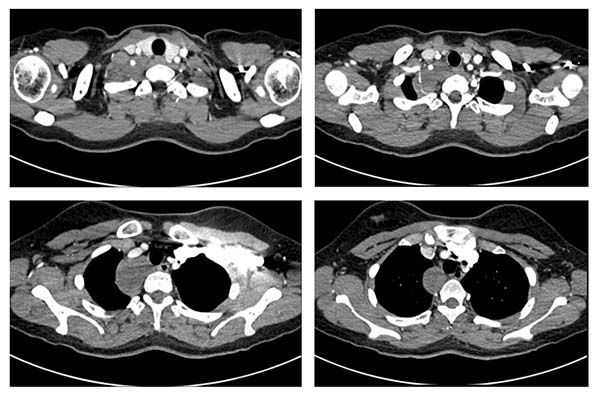

患者是一名来自新疆的19岁女生,在校期间一次常规体检中偶然发现后纵隔肿物。因肿物位置特殊,患者及家属在当地多家医院辗转求医,最终慕名到省立医院刘相燕主任处就诊。入院后,患者完善了胸部CT平扫+增强检查,影像显示,肿物上缘至甲状腺水平,向下沿气管及食管走行,累及长度近6厘米,与右锁骨下动脉关系密切,几乎完全包绕椎动脉。此外,肿瘤已累及交感神经,紧邻臂丛神经,术中稍有不慎极易损伤重要的血管、神经,导致严重的并发症。这极大增加了手术难度与风险,对手术团队提出了挑战。针对患者复杂的病情,刘相燕主任带领团队制定了详尽的手术方案,就手术切口选择、术中突发状况应急处理以及术后生命体征与神经功能监测等环节均进行了充分讨论与周密准备。

患者术前胸部增强CT影像资料

经过充分的术前评估与积极准备,患者及时接受了手术治疗。因患者肿瘤与周围重要血管、神经界限不清,同时,由于胸廓出口位置特殊,血管及神经显露困难,手术操作空间严重受限。术中,刘相燕主任结合术前增强CT影像精准确认并逐一离断肿瘤的多支滋养动脉,将血管、神经充分游离后完整切除肿瘤,并完整保留相关血管、神经功能。整台手术历时三个多小时,最终顺利完成。患者术后恢复良好,术后第6天便顺利出院返回新疆,目前已恢复正常的学习和生活。